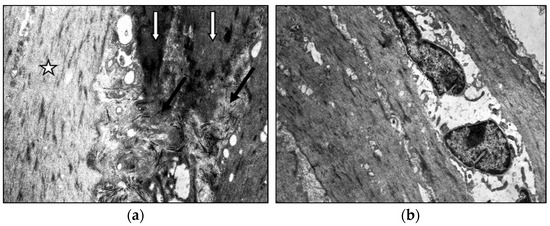

Age- and Varicose Disease-Associated Changes in the Muscular Components of the Great Saphenous Vein

by Khurshed A. Abduvosidov, Irina A. Chekmareva, Valeria G. Shestakova, Irina N. Shabanova, Alexander G. Alekseev, Edgar S. Kafarov, Alexander A. Palalov, Irina N. Yashina and Evgeny N. Galeysya

J. Clin. Med. 2025, 14(18), 6448; https://doi.org/10.3390/jcm14186448 - 12 Sep 2025

Varicose disease and other age-related vascular illnesses are extremely prevalent among the adult population. Despite this, research devoted to involutive changes in the veins of the lower extremities is rare and fragmented. Complex morphological evaluation of the wall of the vein related to [...] Read more.

Varicose disease and other age-related vascular illnesses are extremely prevalent among the adult population. Despite this, research devoted to involutive changes in the veins of the lower extremities is rare and fragmented. Complex morphological evaluation of the wall of the vein related to age and varicose disease can add valuable data to fundamental geriatric and vascular medicine. Objectives: The study was designed to determine the age-related changes in the muscular component of the great saphenous vein and changes associated with varicose disease. Materials and Methods: A morphological study of a specimen of the great saphenous vein was conducted on 55 deceased individuals and 80 patients with varicose disease. Four age subgroups were identified: young, middle-aged, elderly, and senile. A total of 135 fragments of the great saphenous vein were evaluated. Histological, morphometric, and electron microscopic studies were performed. A quantitative analysis of the volumetric fraction of muscular components was calculated using the Shapiro–Wilk test, Kruskal–Wallis (ANOVA) and Mann–Whitney methods with Bonferroni correction. Results: Our study showed that the amount of connective tissue elements between bundles of smooth muscle cells increased with age. In patients with varicose disease, we observed an appearance of connective tissue fibers among smooth muscle cells, more pronounced with the disease progression. The structure of smooth muscle cell changes. Thus, we observed hypertrophy and phenotypic heterogeneity of cells with subsequent destruction of communicative contacts. The values of subintimal longitudinally arranged smooth muscle cells reached their maximum in middle age in both normal and varicose veins, while significant decrease occurred in elderly and senile patients. Quantitative indicators of circularly arranged smooth muscle cells of the middle layer did not change with age but significantly decreased in varicose disease. Age-related changes are characterized by an increase in the proportion of smooth muscle cells in the outer layer. In varicose veins, in young and middle-aged patients, the content of bundles of longitudinally arranged smooth muscle cells in the outer layer was higher compared to the age norm, with a significant decrease in senile age. Conclusions: The age norm of the muscular component of the great saphenous vein wall is characterized by an increase in the volumetric fraction of subintimal longitudinally arranged smooth muscle cells in middle age, the volumetric fraction of circularly arranged smooth muscle cells of the middle layer remains unchanged, and the volumetric fraction of bundles of longitudinally arranged myocytes of the outer layer increases. With age in varicose disease, sclerotic changes progress in the structure of the great saphenous vein at the tissue, cellular, and intracellular levels, leading to a decrease in the volumetric fraction of all muscular components of the great saphenous vein structure. Full article

Show Figures

Figure 1